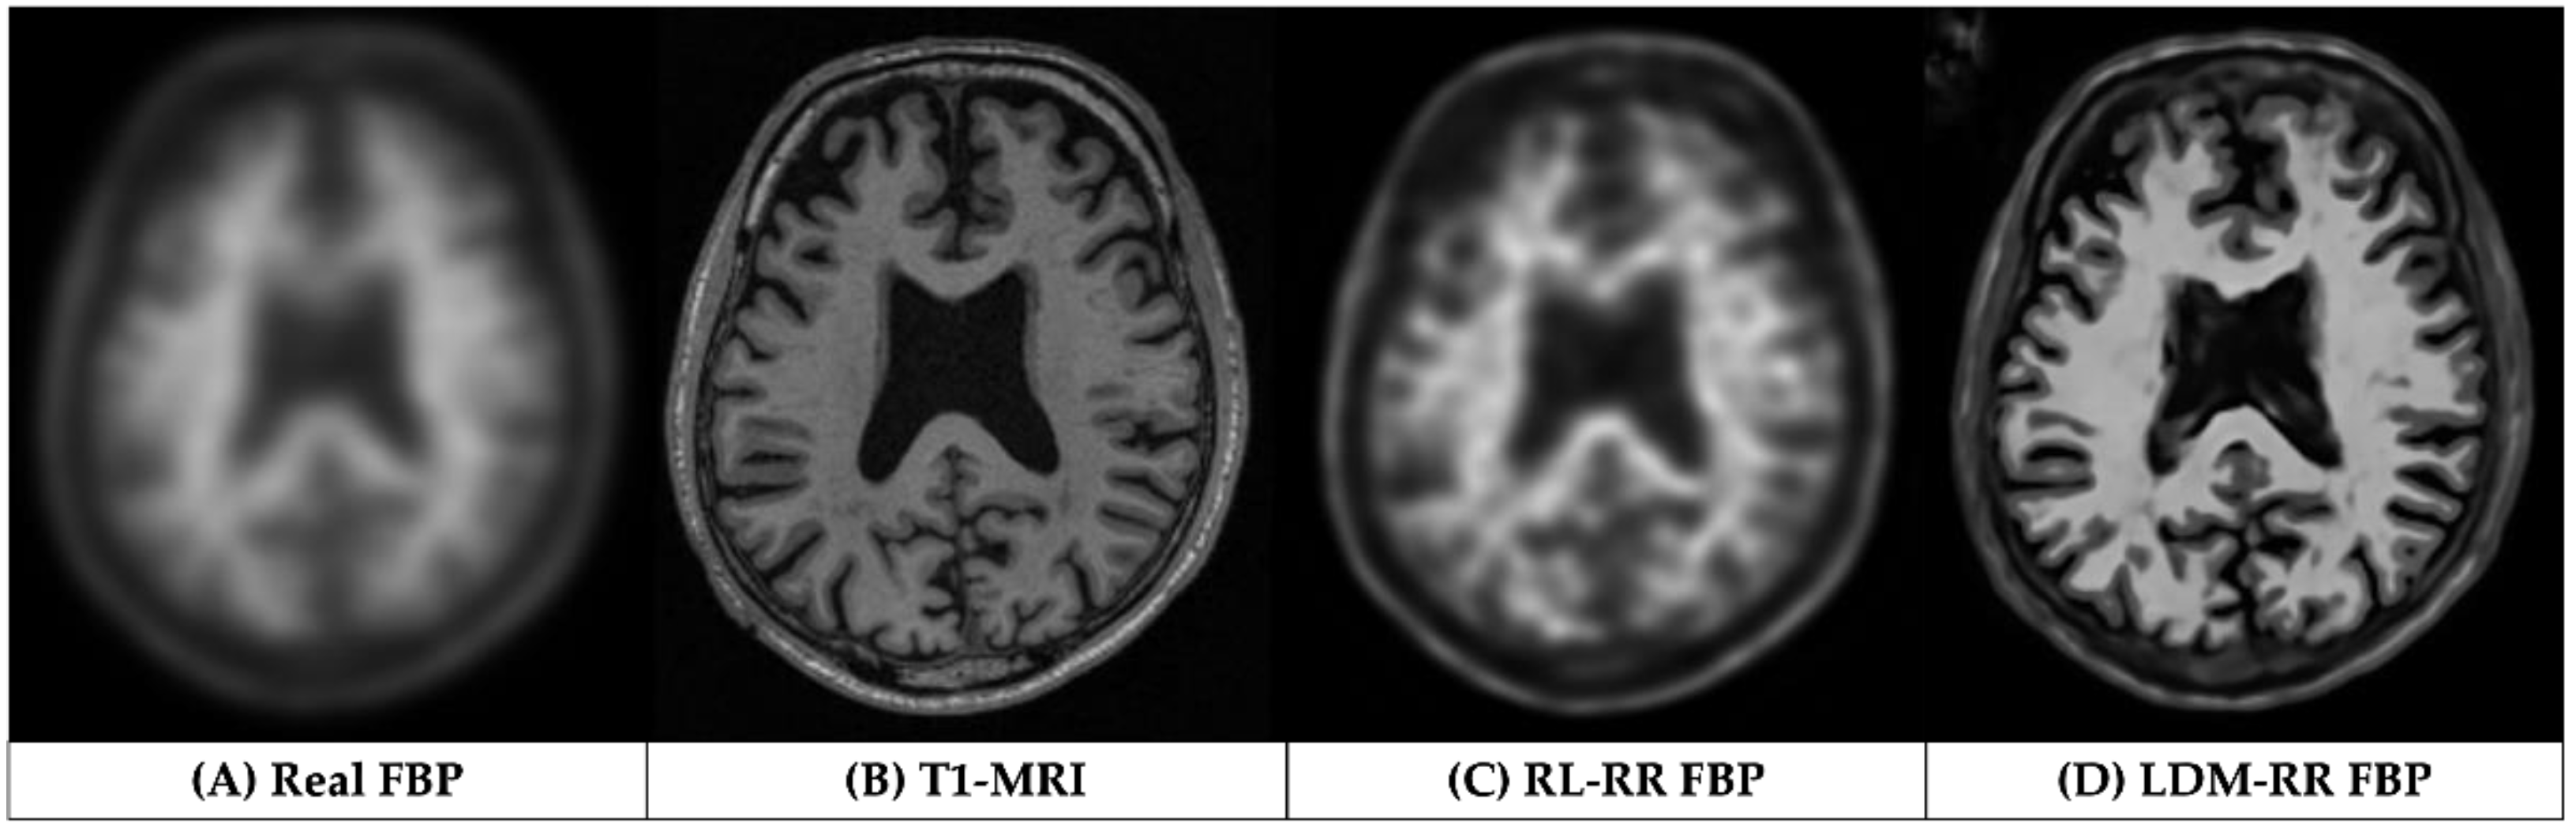

3.1. Qualitative Assessments